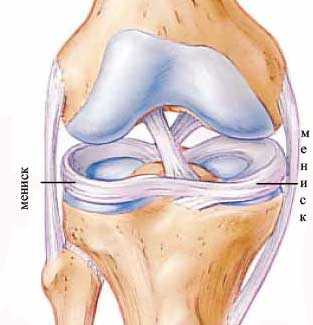

Суставная щель коленного сустава содержит парные хрящевые структуры, которые имеют название мениски. Выделяется латеральный (наружный) и медиальный (внутренний мениск). Они имеют форму полумесяца и состоят из более широкого тела, переднего и заднего рогов. Данные структуры выполняют важные функции, они обеспечивают стабилизацию и амортизацию сустава.

Наружный мениск закреплен менее жестко, при механическом воздействии он может смещаться, поэтому его повреждения развиваются реже. Внутренний мениск закреплен более жестко, поэтому при чрезмерных воздействиях он более легко и часто подвергается повреждению.

Так как рога менисков содержат в себе меньший объем хрящевой ткани, то нарушение целостности обычно имеет место в области их локализации. Более выраженное механическое воздействие может вызвать повреждение мениска в области рогов и тела.

Колено имеет сложное строение. Сустав включает поверхности мыщелков бедренной кости, впадины голени, а также надколенник. Для лучшей стабилизации, амортизации и снижения нагрузки в суставной щели локализуются парные хрящевые образования, которые называются медиальный (внутренний) и латеральный (наружный) мениски. Они имеют форму полумесяца, суженные края которого направлены вперед и назад – передние и задние рога.

Наружный мениск является более подвижным образованием, поэтому при чрезмерном механическом воздействии он немного смещается, что предотвращает его травматическое повреждение. Медиальный мениск закреплен связками более жестко, при воздействии механической силы он не смещается, вследствие чего более часто происходит повреждение в различных отделах, в частности в области заднего рога.

Для стабилизации, амортизации колена в щели располагается два хрящевых компонента. Они называются латеральный (наружный) и медиальный (внутренний) мениск. Они напоминают полумесяц.

Широкое тело имеет небольшие сужения, направленные кпереди и кзади и называющиеся рогами. Такое строение позволяет колену выдерживать относительно высокие нагрузки, обусловленные давлением массы тела на нижние конечности.